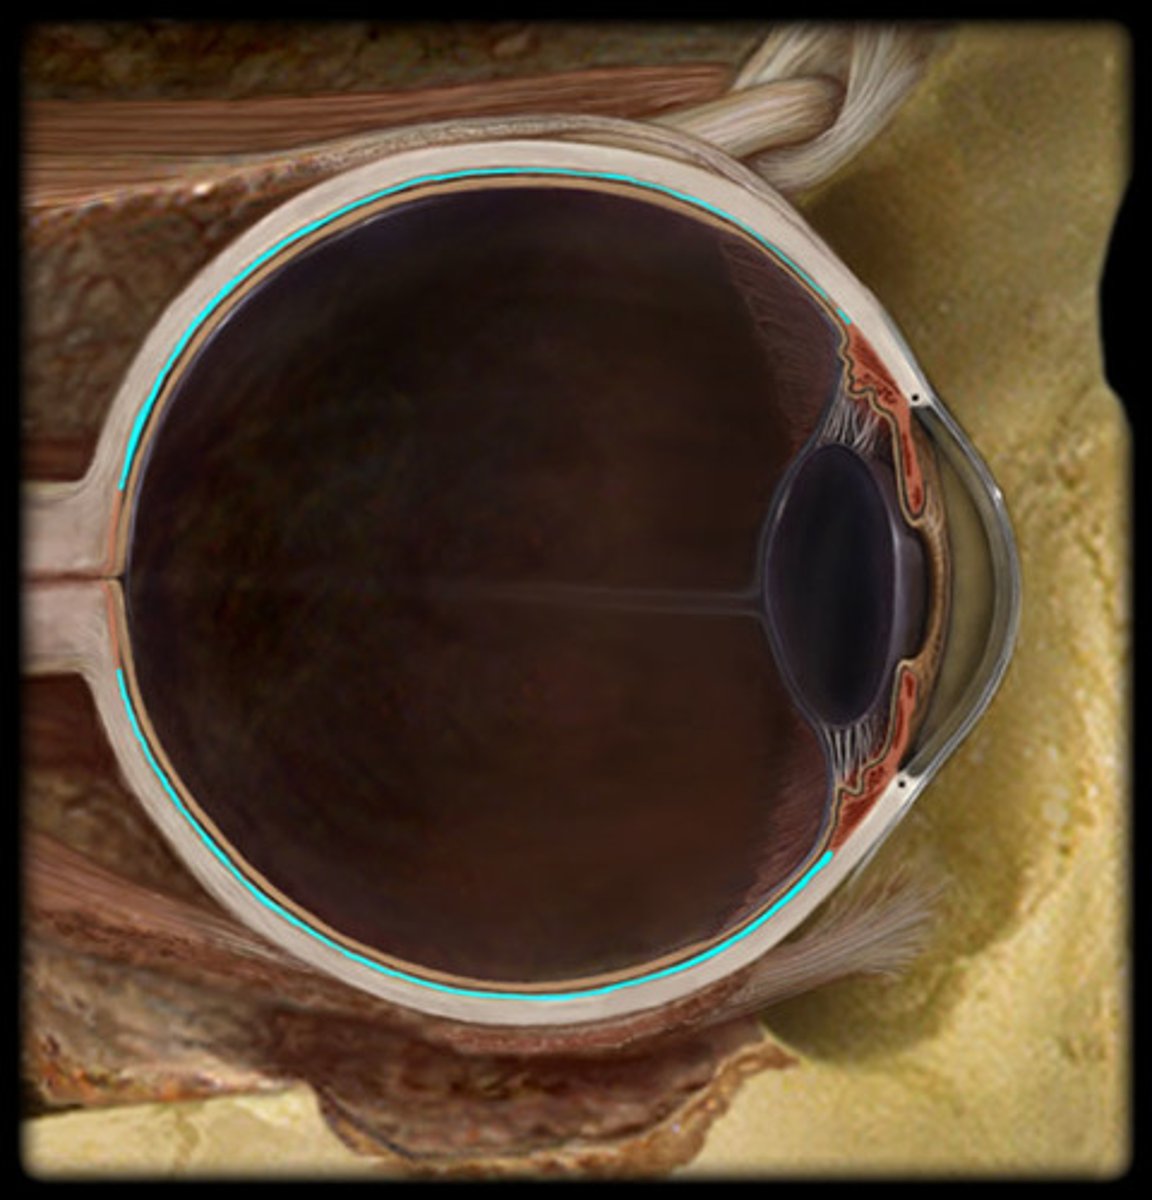

choroid

Sclera

Retina

ciliary body